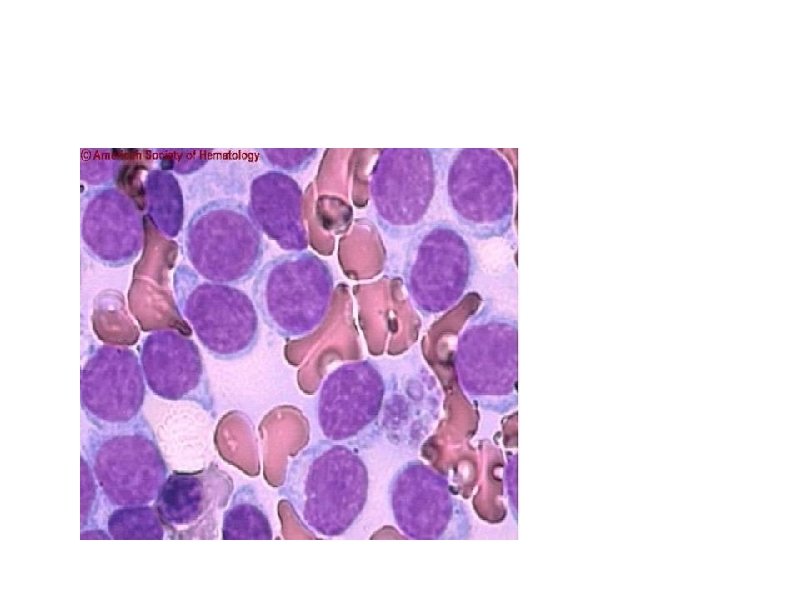

Атипичный лимфоцит (клетка Сезари)